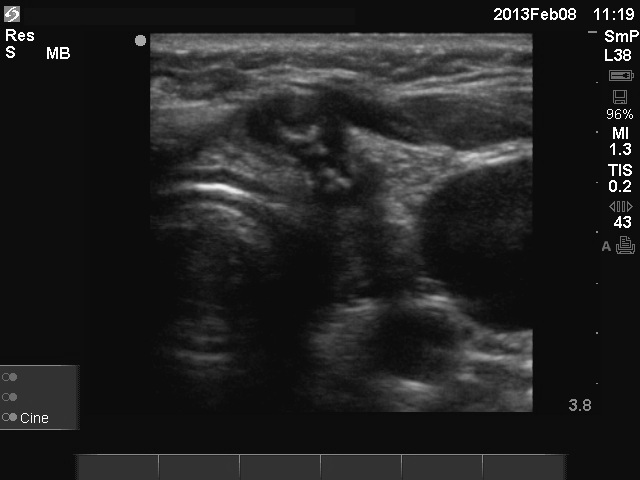

Granulation around surgical thread (cytological diagnosis) - case 1475

There are two granulations both in the left, horizontal and in the right, longitudinal images (arrows). The shape of the masses is irregular. The granulations are hypoechogenic and have one or more echonormal foci.